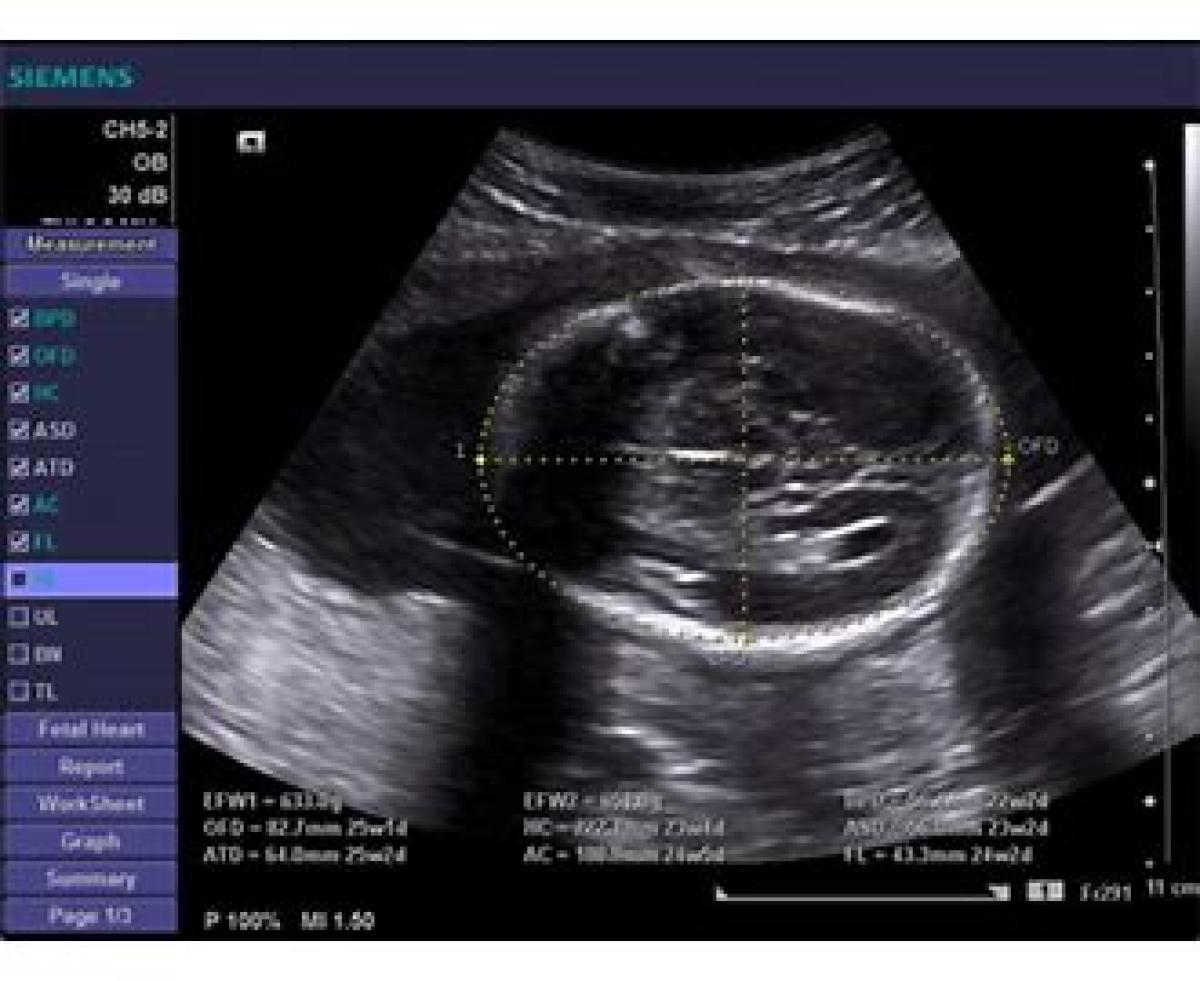

AC به معنی محدوده شکمی است. تنها اندازه گیری مهم در اواخر بارداری محسوب میشود. این پارامتر بیشتر اندازه و وزن جنین را نشان می دهد تا سن آن را اندازه گیری های دوره ای منظم برای نظارت بر رشد جنین مفید هستند. از این پارامتر برای تعیین زمان زایمان استفاده نمیشود.